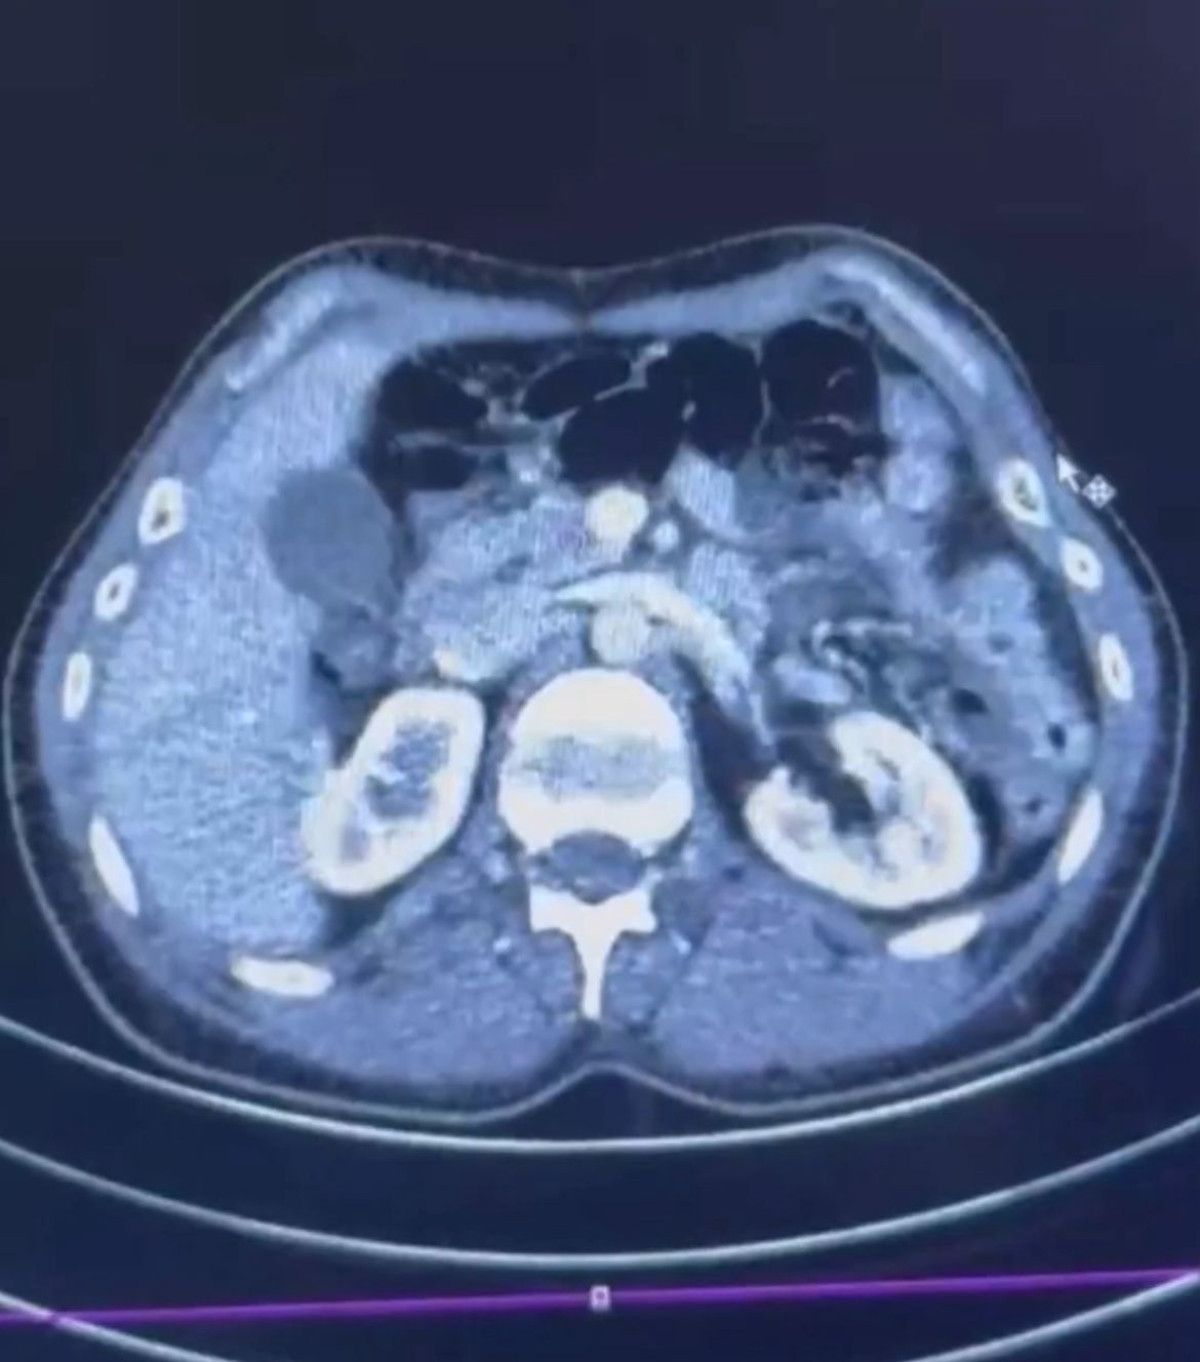

Hastanede yapılan röntgen ve ultrason incelemelerinde, iki şüphelinin midesinde yaklaşık 50 kapsül halinde toplam 554 gram uyuşturucu bulundu.

Uyuşturucu maddeler, sağlık ekiplerinin uyguladığı tedaviyle çıkarıldı. Soruşturma çerçevesinde gözaltındaki üç şüphelinin emniyetteki işlemleri devam ediyor.